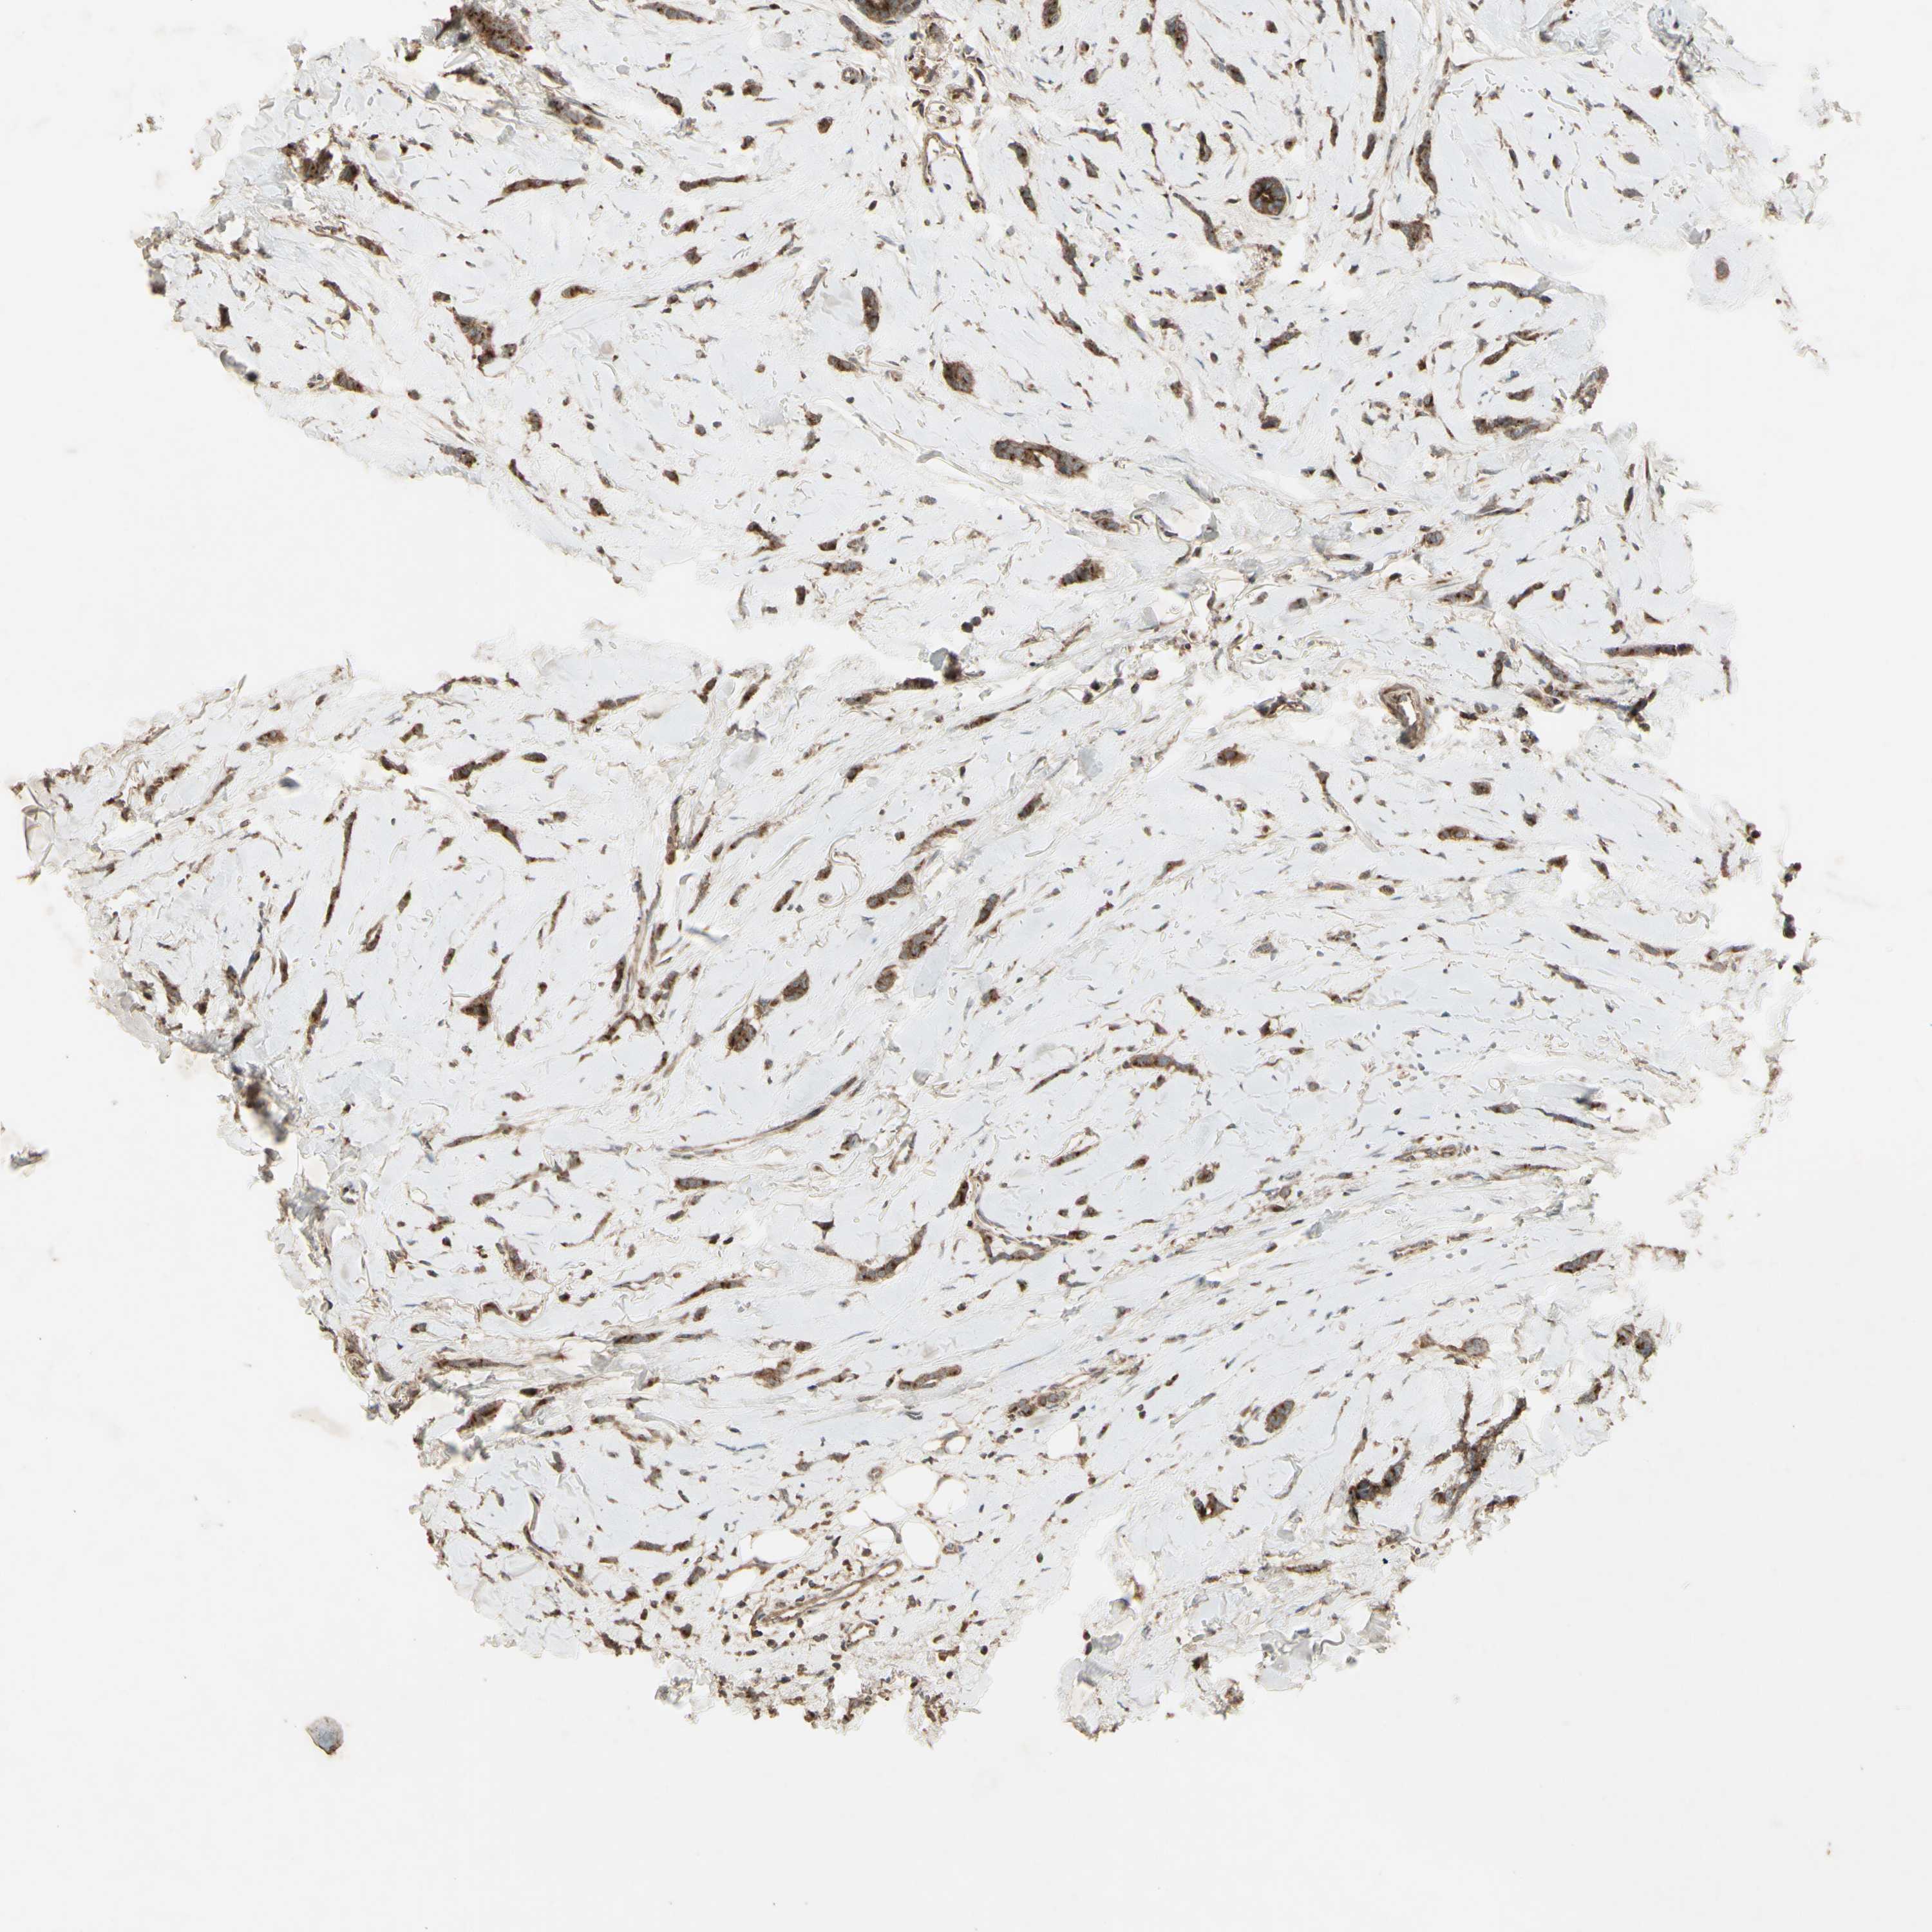

CANCER BREAST CANCER Show tissue menu

Breast cancer

Human cancer